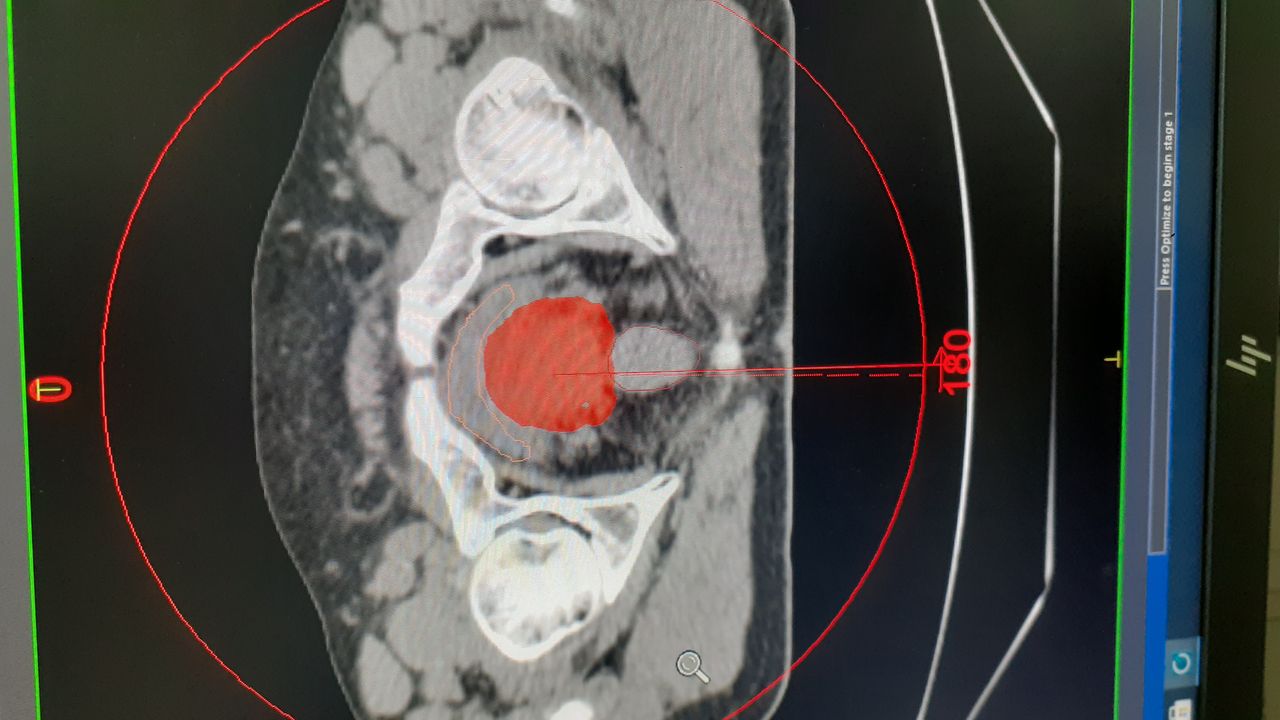

• Terapia de arco volumetrico modulado (VMAT)